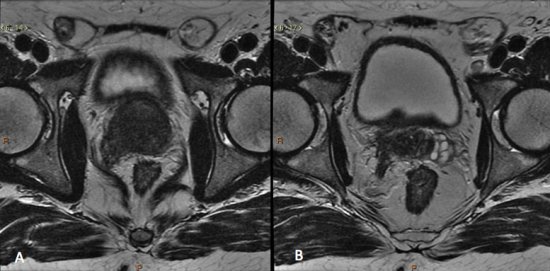

Sequências multiplanares ponderadas em T2 são fundamentais para o estudo da próstata, pois apresentam a maior resolução espacial e de contraste, permitindo avaliação detalhada da anatomia prostática. Nas imagens pesadas em T2, a zona periférica normal tem hipersinal homogêneo, apresentando-se em formato de “crescente” no plano axial. As zonas transicional, central e periuretral, dificilmente diferenciadas por métodos de imagem são, em conjunto, denominadas glândula central ou glândula interna, e exibem intensidade de sinal intermediária em T2. O limite entre a zona periférica e a glândula central é denominado “cápsula cirúrgica”, e a camada fibromuscular descontínua que recobre a glândula, “cápsula prostática”.11(fig. 3).

Figura 3. Imagens de RM ponderadas em T2 demonstrando a anatomia prostática. A) Próstata normal. A zona periférica (ZP) exibe hipersinal homogêneo, e a glândula central (GC) apresenta sinal intermediário. B) Hiperplasia prostática benigna. Observe o aumento significativo das dimensões da glândula central (GC), que exibe sinal heterogêneo e aspecto nodular. O limite entre a zona periférica e a glândula central é denominado cápsula cirúrgica, e linha de baixo sinal circundando a próstata é denominada cápsula prostática (setas).

Na zona periférica da próstata, os tumores clinicamente significantes usualmente se apresentam como nódulo ou área mal definida de baixo sinal nas imagens ponderadas em T2. (fig. 4).

Figura 4. Imagem axial de RM da próstata ponderada em T2. Nódulo bem delimitado com baixo sinal na zona periférica esquerda, de alta probabilidade de neoplasia clinicamente significativa.

Este achado tem alta sensibilidade na detecção de câncer de próstata com valores de Gleason de 7 ou mais, porém não é específico, e pode ser encontrado em diversas condições, como prostatite, hemorragia, atrofia, cicatrizes e pós-tratamentos.15

O diagnóstico de câncer de próstata na glândula central é um desafio, dada a heterogeneidade da região, e o amplo espectro de alterações relacionadas a hiperplasia prostática benigna. Pode-se suspeitar de tumores de glândula central pela presença de área homogeneamente hipointensa em T2, com margens mal definidas ou espiculadas, de forma lenticular, ou quando está associado a indefinição da cápsula cirúrgica, invasão da uretra ou do estroma fibromuscular anterior.15

No estadiamento locorregional do câncer de próstata, o aspecto mais relevante na tomada de decisão terapêutica é a diferenciação entre tumor confinado ao órgão (T1 e T2) e tumor localmente avançado, sob as formas de extensão extracapsular (T3a) ou invasão de vesículas seminais (T3b). Para esta avaliação, as imagens ponderadas em T2 são as mais indicadas15,18(fig. 5 e 6).

Figura 5. Estadiamento de adenocarcinoma de próstata Gleason 7. Imagem ponderada em T2 evidencia nódulo no terço médio da zona periférica direita, notando-se pequena irregularidade da cápsula prostática adjacente à lesão, sugestivo de extensão extra-capsular.

Figura 6. Estadiamento de adenocarcinoma da próstata Gleason 9. A) Lesão hipointensa comprometendo quase toda a glândula, com extensão para a gordura periprostática à direita. B) Comprometimento das vesículas seminais.

Os critérios de imagem para extensão extracapsular incluem assimetria ou envolvimento macroscópico dos feixes neurovasculares, abaulamento focal do contorno prostático, espiculação ou irregularidade do contorno prostático, obliteração do ângulo retoprostático, retração capsular, e sinais de rotura capsular com extensão direta a gordura periprostática. Lesões que exibem contato maior que 1,0 cm com a cápsula prostática apresentam maior risco de extensão extracapsular.15,18

Os achados que indicam invasão das vesículas seminais incluem: aumento de tamanho, assimetria e hipointensidade das vesículas seminais, obliteração do ângulo vesicoprostático e extensão direta da base prostática à vesícula seminal, sendo este achado o de maior valor preditivo positivo.15,18